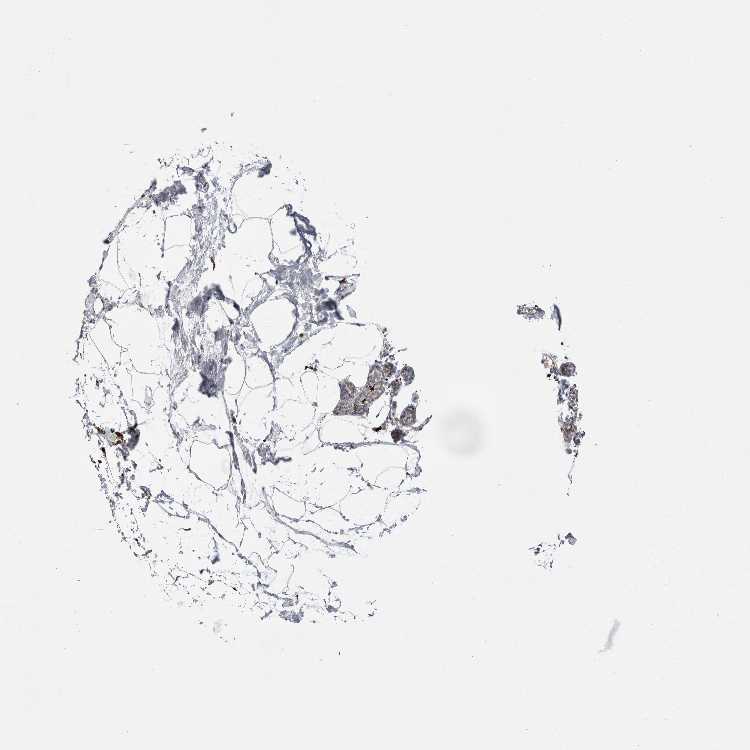

Antibody staining in the annotated cell types in the current human tissue is reported as not detected, low, medium, or high. This score is based on the staining intensity and fraction of stained cells.

Information about each individual sample is listed below, including gender, age, a tissue section image and estimated fractions of cell types. pTPM (transcripts per million) values give a quantification of the gene abundance which is comparable between different genes and samples.